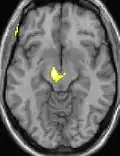

La morphométrie voxel par voxel (VBM) montre les différences structurelles des zones du cerveau

Les images par tomographie à émission de positron indiquent les régions du cerveau qui sont activées lors de la douleur, par rapport aux périodes sans douleur. Elles montrent les régions du cerveau qui sont toujours actives durant la douleur en jaune/orange (appelé "matrice-douleur"). La zone au centre (dans les trois vues) est spécifiquement activée uniquement pendant la crise. Les photos sur la ligne du bas (effectuées par VBM) montrent les différences structurelles entre les patients souffrant d'AVF et des personnes saines : seulement une partie de l'hypothalamus est différente[50],[51].

Il semble exister des anomalies microstructurales hypothalamiques bilatérales (en l'occurrence l'existence d'une hypertrophie)[52] sans que l'on sache si ces anomalies sont la cause ou la conséquence de la répétition des crises.